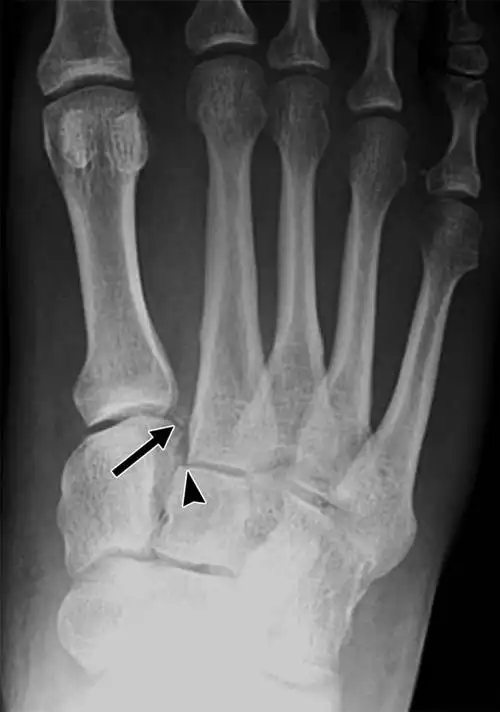

第五跖骨基底部裂纹骨折忧伤记录